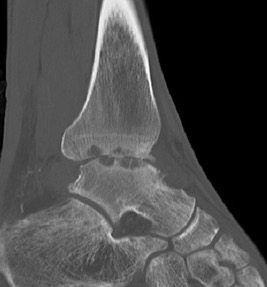

CT

Small anterior tibial spur

Large cysts in patient with ankle OA